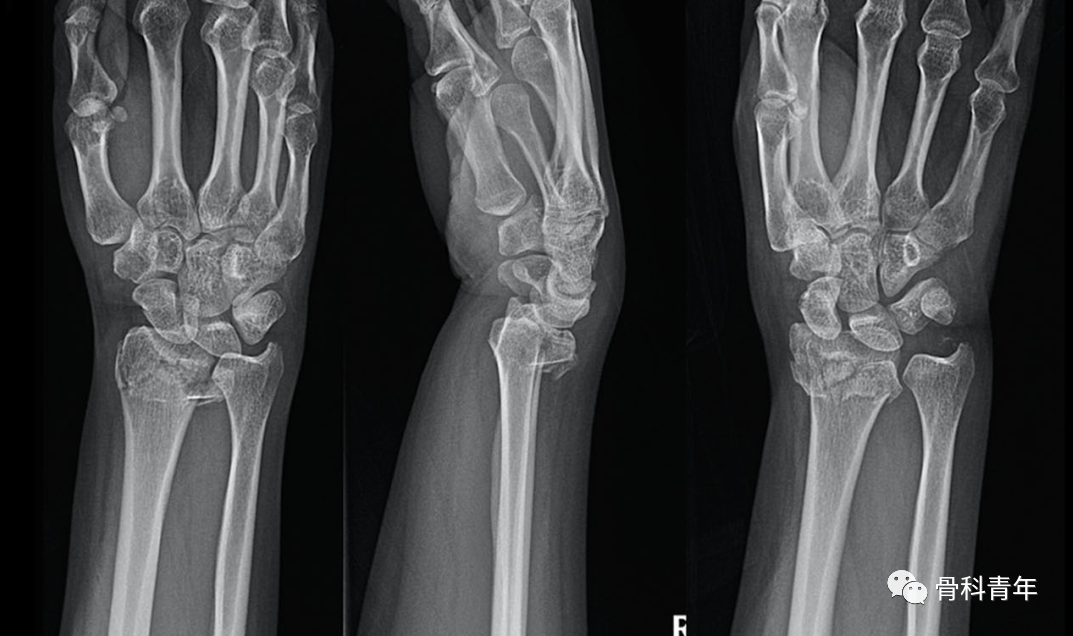

掌侧锁定加压接骨板(Volar locking compression plate,LCP)内固定是桡骨远端骨折治疗的金标准,但LCP并非对所有桡骨远端骨折均实用,如桡骨极远端骨折、背侧缘骨折、掌侧die-punch骨折等;同时,LCP钢板也存在较多的并发症,包括旋前方肌损伤、骨折血运破坏、掌侧软组织激惹、背侧肌腱磨损等,同时对严重骨质疏松患者存在较高的内固定失效风险。

对降低术后并发症和减少医源性损伤的需求,催生了各种新型内固定方式的发展。本文简要介绍4种新型内固定方式,供临床医生参考。